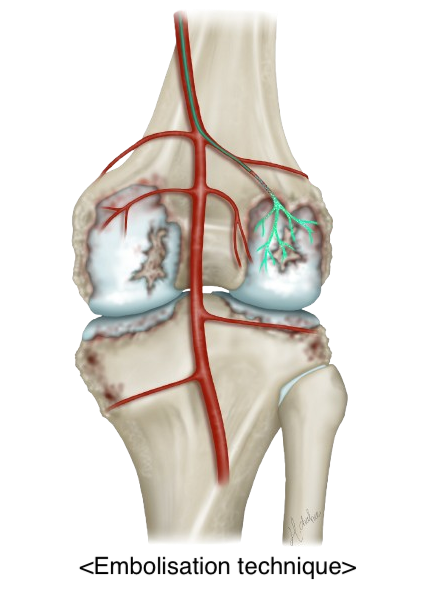

Genicular Artery Embolization (GAE) is a minimally invasive, image-guided procedure for treating chronic knee pain caused by osteoarthritis or related to chronic inflammation. It works by reducing blood flow to the inflamed areas of the knee, which can help relieve pain and improve mobility. Interventional radiologists will insert a small catheter (a thin hollow tube) into the artery of the patient’s upper thigh and, with the use of X-rays, guide the catheter to the arteries supplying the lining of the knee. Tiny particles are then injected through the catheter into these arteries, reducing the blood supply. This in turn reduces the inflammation associated with osteoarthritis, which alleviates the pain

- Tiny microparticles are injected to block the abnormal vessels while maintaining normal blood flow